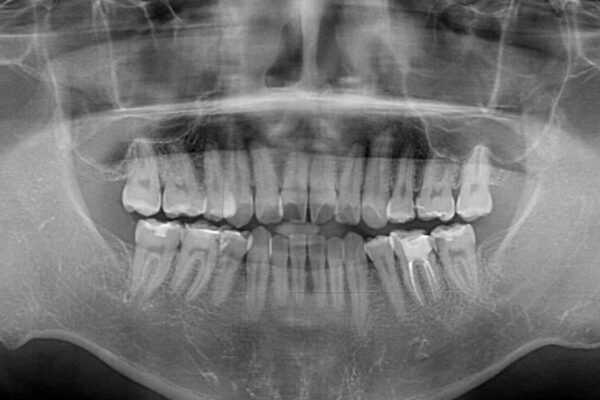

高校時代に行った抜歯矯正が後戻りをしたとのことで来院された患者様です。

再矯正であることから、目立ちにくい装置を希望されたため、インビザラインにて矯正治療を行うこととしました。

治療前

• 後戻りでデコボコの前歯 インビザライン矯正治療 治療前画像